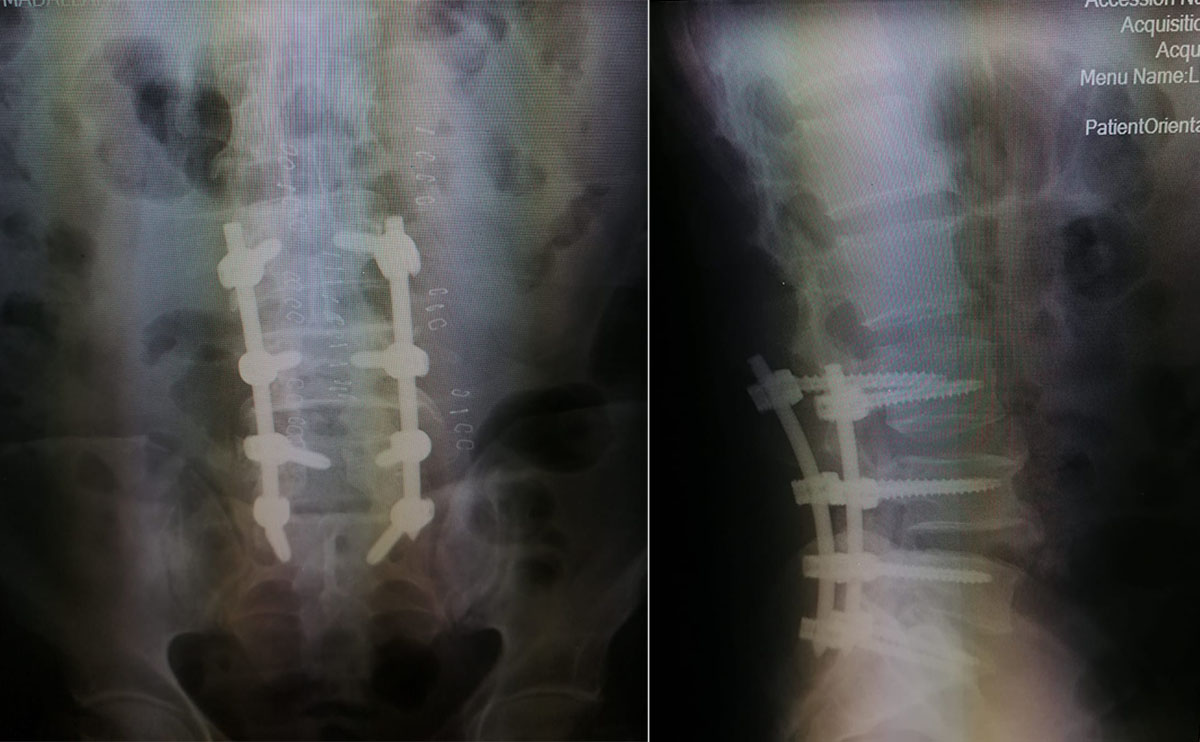

عمانيات - أجريت في مستشفى الكرك الحكومي، عملية تثبيت عبر ثقوب صغيرة بالجلد بالتداخل المحدود، مع إجراء إعادة تحرير لقناة العصب والأعصاب الطرفية من خلال الميكروسكوب ( percautanious 4 level spinal fusion with revision microscopic (lamenectomy لمريض يعاني من ألم شديد أسفل الظهر و خدران في الأطراف مع عدم ثباتية في الفقرات القطنية بالرغم من إجراء عملية سابقة له في مستشفى آخر.

وبين مدير المستشفى الدكتور معتز القرالة في بيان اليوم الجمعة، أن المريض بحالة صحية جيدة وعاد إلى منزله بعد 3 أيام من العملية، لافتا إلى أن هذه العملية تجرى لأول مرة في محافظات الجنوب وفي وزارة الصحة.